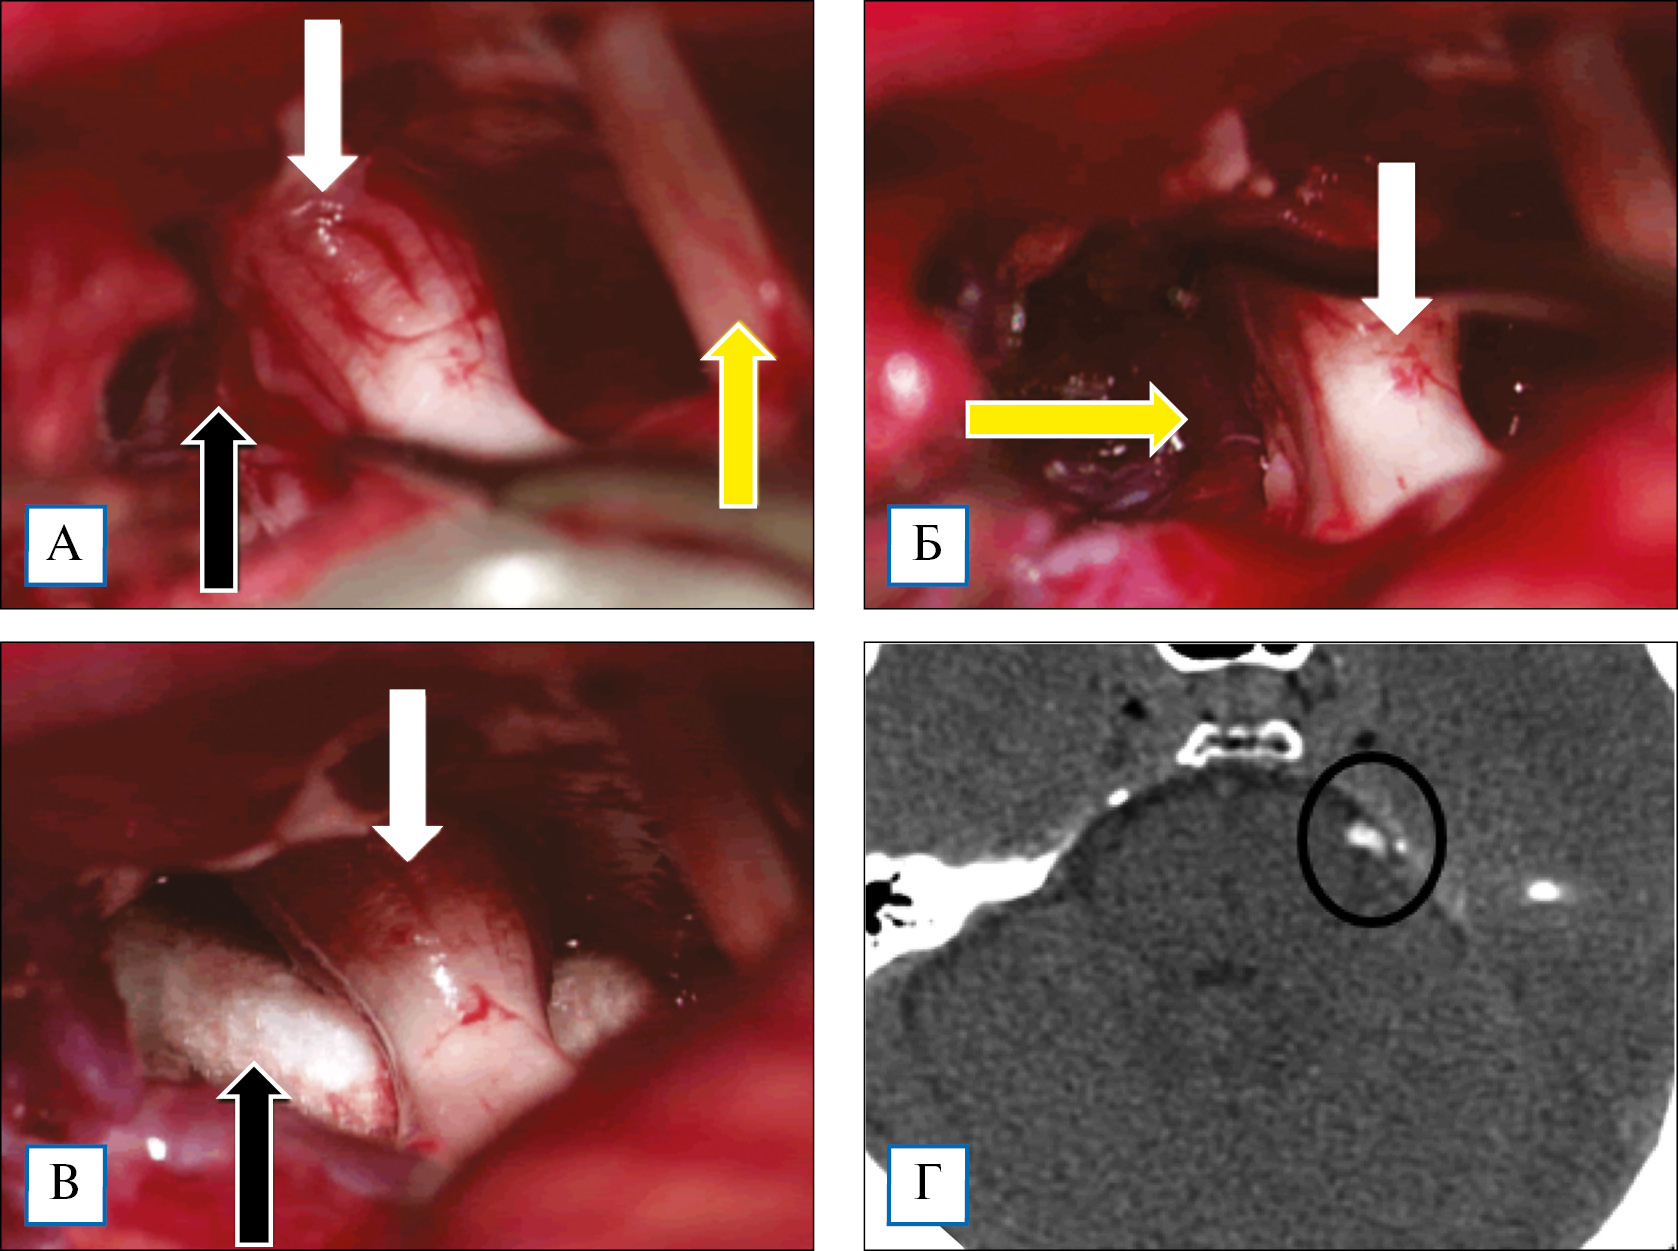

Операцию проводили в положении пациента на животе с поворотом головы в сторону операции на 15–20°. Применяли ретросигмовидный доступ; на интракраниальном этапе у 9 (14,5%) пациентов кроме микроскопа дополнительно использовали видеоэндоскопию компании Karl Storz (Германия) диаметром 4 мм и углом обзора 30° и 70°. В 51 (82,3%) случае выполнена костно-пластическая трепанация черепа, в остальных — резекционная. Видеоэндоскопия позволила визуализировать зону выхода корешка тройничного нерва и компримирующие сосуды на вентральной поверхности корешка тройничного нерва. После обнаружения нейроваскулярного конфликта проведена диссекция сосудов от корешка тройничного нерва с последующей установкой тефлоновой прокладки между ними (рис. 2).

Рис. 2. Пациент М. с невралгией тройничного нерва: этапы микроваскулярной декомпрессии и послеоперационные снимки компьютерной томографии

Примечание. Интраоперационные снимки: А — корешок тройничного нерва (стрелка белого цвета), выраженный спаечный процесс (стрелка черного цвета), лицевой нерв (стрелка желтого цвета); Б — корешок тройничного нерва (стрелка белого цвета), верхняя мозжечковая артерия (стрелка желтого цвета); В — корешок тройничного нерва (стрелка белого цвета), тефлоновая прокладка (стрелка черного цвета); Г — послеоперационные снимки компьютерной томографии, на которых визуализирована тефлоновая прокладка в проекции корешка тройничного нерва (отмечено кругом).